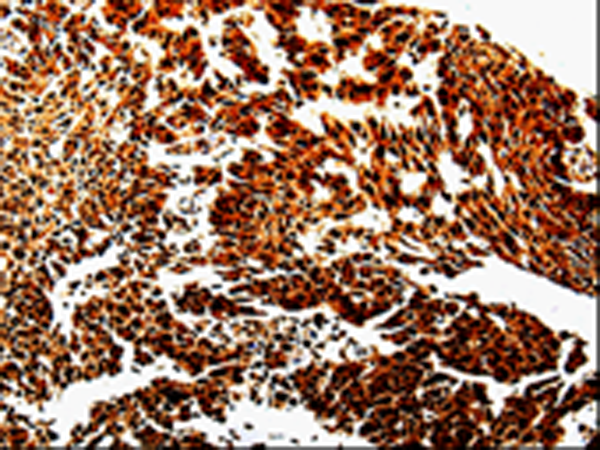

分类: 科研抗体货号: P00147别名: ANG3; ARP1; AngY; ANGPT3; UNQ162; dJ595C2.2应用: IHC反应种属: Human, Mouse